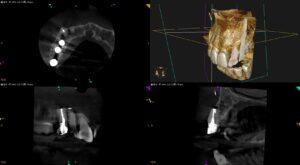

紹介患者さんの治療。 主訴は、 右上犬歯の違和感と疼痛 である。 なぜこのような用語が出てくるか?といえば、患者さんは実は同じ医療従事者の方(看護師さん)であった。 紹介元の先生からは、眼窩下孔にGutta Percha … 続きを読む Apicoectomyは、“素人”がやれるほど簡単な歯科医療なのだろうか?〜#6 Apicoectomy